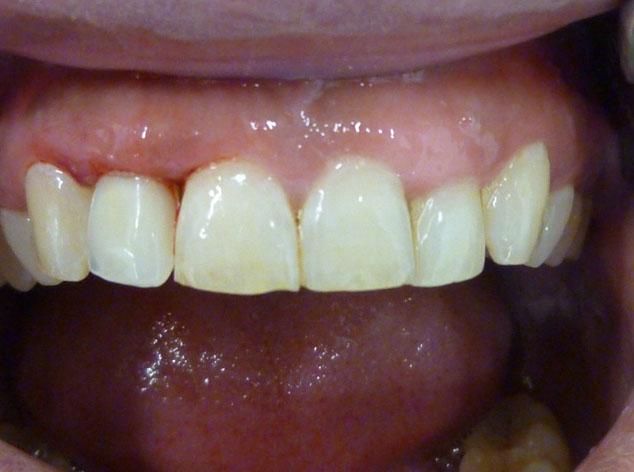

En estos casos han sido tratados con la filosofía de all-at-once, en la

misma sesión: